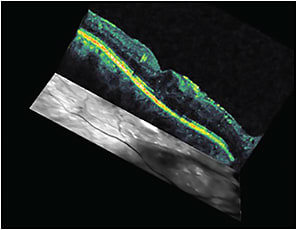

At the first visit, ordering OCT (particularly when best-corrected visual acuity is less than 20/20) is important because it will help us to document and learn about the pattern, location, thickness (Figures 1 and 2), and vitreomacular interface status of the edema, all of which can affect our treatment plan and visual prognosis.

Figure 2. Three-dimensional OCT map of DME before treatment.

OCT can be ordered again after 18 weeks based on treatment plan (Figures 3 and 4), to monitor the effectiveness of treatment. Further, it can help us decide whether it is mandatory to change, stop, or continue with the treatment plan.

Figure 4. Three-dimensional OCT map for the patient in Figures 1, 2, and 3, after four anti-VEGF injections.